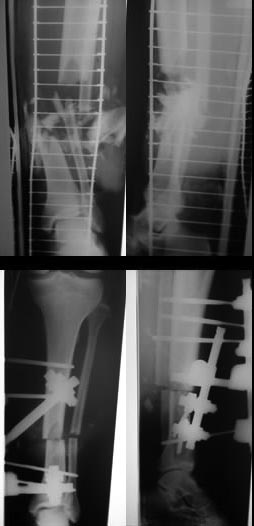

6 сутки после травмы

на сегодняшний день

Учитывая положение дел на сегодняшний день. На фото. Можно наложить ап. Илизарову , думаю одной остеотомии в верхней трети большеберцовый кости , будет достаточно для удлинения на 9.0см. И свободная кожная аутопластика .

Даниил 01 Июль 2016, 12:09

Сегодня на перевязке при некрэктомии обнажилась большеберцовая кость - планируем выполнить пластику кожнофасциальным лоскутом с левой голени для укрытия деффекта.